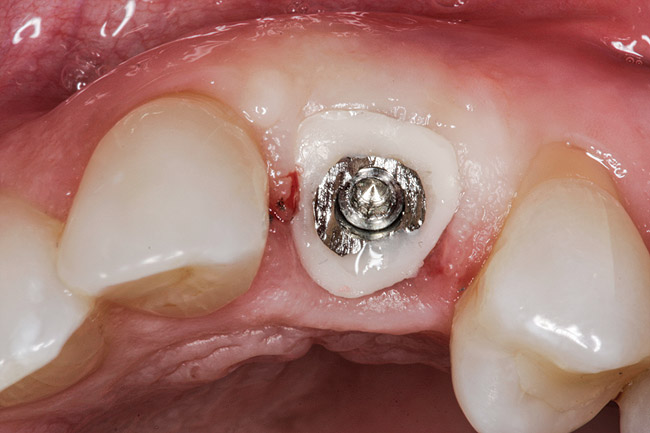

Figure 9 shows a custom healing abutment in place; notice the blanching present upon insertion. This reflects the amount of tissue slumping that existed in the short time it took to fabricate the custom healing abutment. An advantage of this type of healing abutment is that it allows a removable provisional restoration to be made for the patient. The main shortcoming of the removable type of provisional, however, is that the soft-tissue support gained from the pontic is only present while the provisional is worn, making this approach highly dependent on patient compliance. If the patient leaves the provisional out for extended periods of time or loses it, the soft tissue will no longer be held in the proper relationship. By having the custom healing abutment underneath the removable prosthesis, the soft tissues are always being held in the proper position. It can also be used under bonded provisionals as well.

Fig 9. Custom healing abutment in place, with blanching present upon insertion.

Figure 9